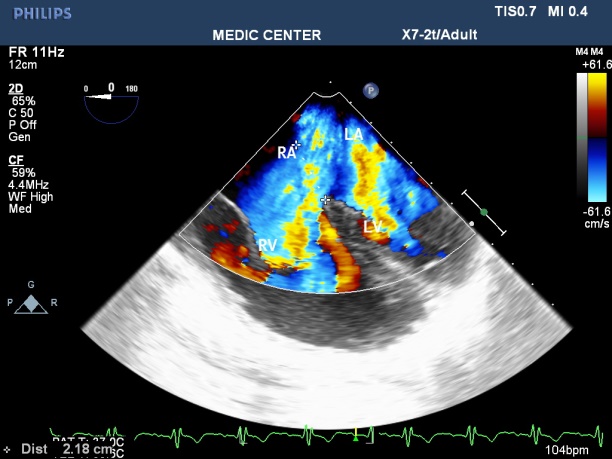

Among 204 Pts with ASD, The secundum defects account for approximately 78%, then primum ASDs 6%, sinus venosus ASDs 12%, multiple shunt ASD 4%, unroofed coronary sinus not seen. 3D TEE can assess the size of ASD and the circumferential rims to select Patients for Transcatether closure. Currently we perform ASD closure limited to ASDs less than 30mm and with at least 5mm of circumferential rims (Table 1).

The X-plan mode can be used to estimate the maximal diameter of defect in two orthogonal planes. Three-dimensional (3D) TEE imaging is an important adjunct to 2D imaging because multiplanar reconstruction ensures that the defect is measured accurately.

Three-dimensional (3D) TEE images can be rotated to demonstrate the defect from the RA or LA side in evaluating the secundum atrial septal defect rims. This improves understanding of their shape and relationships to surrounding intracardiac structures.

In the current area, Live 3D TEE is a usefull complementary tool in assessing the size, site, and shape of an ASD, its rims and realtions with neighboring structures. It is also helful in confirming the good positioning of a device and identifying the site of any residual shunt next to device closure [11].

We always display a true en face view of the defect from the left atrium so that its dimensions can be accurately measured [12]. Three dimensional 3D TEE visualizes clearly the shape and the rims in a view only, that previously were obtained only by many consecutive 2D views. Review of 72 suscessful cases of ASD device closure demonstrates the size of ASD and its rims were always recorded and measured on the 3D TEE view from the left atrium. Three patients with unsuscessfull ASD device closure related to short aortic rim ( from 0 to 3mm ).

Three-Dimensional (3D) TEE enables improved visualization of ASDs using unique en face representation of the interatrial septum. Three-Dimensional (3D) TEE provides the valuable information including shape, size of defect, its rims prior to perform transcatether device closure.